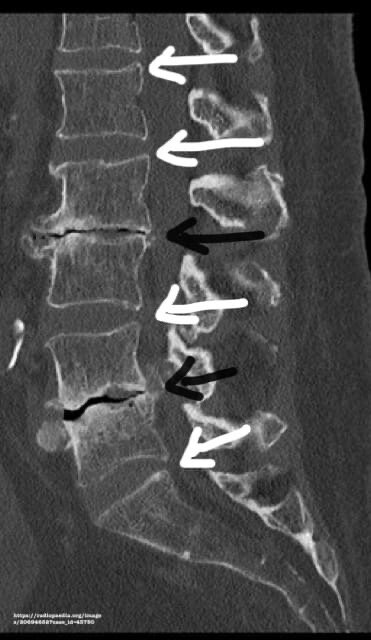

В норме межпозвонковый диск - тугая, компактно собранная структура из фиброзного кольца и пульпозного ядра. Это природный амортизатор. С возрастом или при дистрофических процессах нарушается прочность диска, ослабевают фиброзные волокна - возникает гипермобильность (повышенная подвижность). И именно при движении (форсированном разгибании и сгибании) позвонки расходятся, образуя отрицательное давление в размягченном межпозвонковом диске - формируется пузырёк газа, который мы и видим на снимках КТ в виде чёрного округлого пятна между позвонками. В случае наличия у человека грыжи, «пузырёк» может смещаться в ее сторону и определяться уже в просвете позвоночного канала.

На иллюстрации (КТ поясничного отдела позвоночника): белые стрелки - нормальные межпозвонковые диски, чёрные стрелки - диски с дегенеративными изменениями и полосками газа внутри (чёрные прослойки).